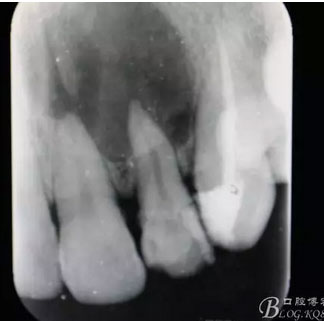

圖1.術(shù)前患者的x光根尖片檢查影像:22根尖完全位于囊腔內(nèi),牙槽骨吸收至嵴頂約5mm。22松動Ⅰ度。